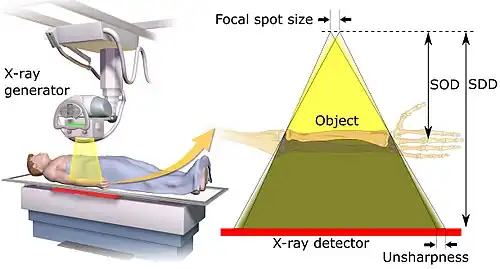

Geometric magnification results from the detector being farther away from the X-ray source than the object. In this regard, the source-detector distance or SDD[3] is a measurement of the distance between the generator and the detector. Alternative names are source[4]/focus to detector/image-receptor[4]/film (latter used when using X-ray film) distance (SID,[4] FID or FRD).

The estimated radiographic magnification factor (ERMF) is the ratio of the source-detector distance (SDD) over the source-object distance (SOD).[5] The size of the object is given as:

,

where Sizeprojection is the size of the projection that the object forms on the detector. On lumbar and chest radiographs, it is anticipated that ERMF is between 1.05 and 1.40.[6] Because of the uncertainty of the true size of objects seen on projectional radiography, their sizes are often compared to other structures within the body, such as dimensions of the vertebrae, or empirically by clinical experience.[7]

The source-detector distance (SDD) is roughly related to the source-object distance (SOD)[8] and the object-detector distance (ODD) by the equation SOD + ODD = SDD.

Geometric unsharpness

Geometric unsharpness is caused by the X-ray generator not creating X-rays from a single point but rather from an area, as can be measured as the focal spot size. Geometric unsharpness increases proportionally to the focal spot size, as well as the estimated radiographic magnification factor (ERMF).